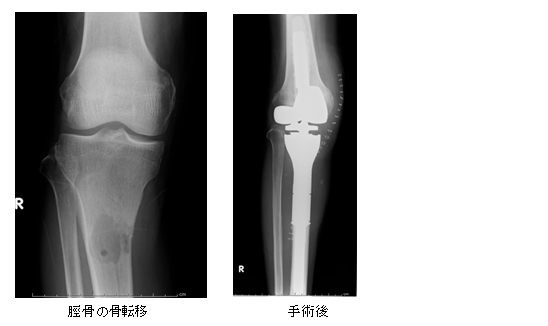

悪性の骨軟部腫瘍の治療は、手術療法を中心に、化学療法(抗癌剤)や放射線療法を組み合わせて行います。悪性骨軟部腫瘍は手術で全て切除する事が基本となりますが、腫瘍そのものだけを取り除いても、腫瘍の周囲に目に見えないくらいの腫瘍細胞が散らばっている事が多いため、再発する可能性が高いです。そのため、腫瘍周囲の一見正常に見える部分も一緒に切除する必要があり、元々存在していた骨や筋肉などが大きく欠損してしまいます。骨が無くなった場合には、無くなった部分を補填するために腫瘍用人工関節を用いたり、腫瘍が存在していた骨を熱処理して再び使用する自家骨移植などを用いることで、患肢温存手術を積極的に行います。また、手術後の筋力低下予防には術後早い段階で足をつけて荷重する事が大事であるため、イリザロフ創外固定器を用い、よりよい機能を目指す治療も行っています。

近年がん治療が進歩した事により、がんを抱えながら社会生活を送られる患者さんも増えてきています。そのため、がんの骨転移患者さんへの治療も、予後と生活の質を考えた治療が必要とされます。当院では他科の医師とがん患者について検討する、キャンサーボードも定期的に開催しており、骨転移患者さんの治療を診療科の垣根を越えて取り組んでいます。